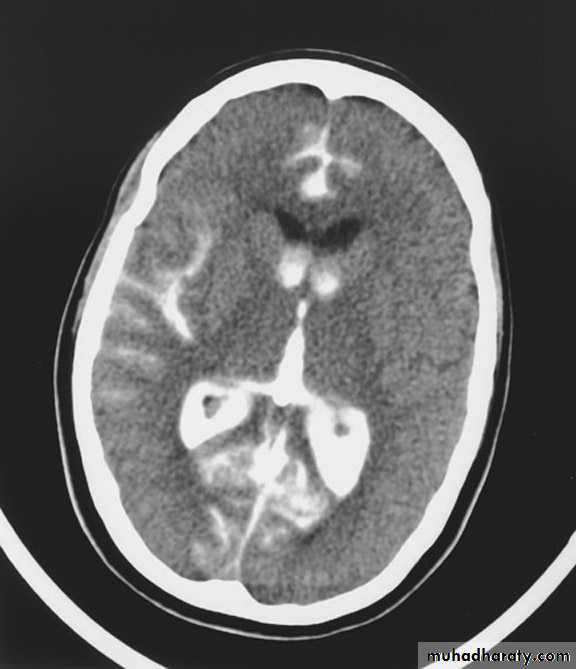

Intra ventricular IVH

Acute Intra cerebral hematoma

CT finding :Hyper dense area , surrounded by edema , any where within the brain parenchyma.

Shifting of the midline

Compression of the ipsi lateral ventricle .